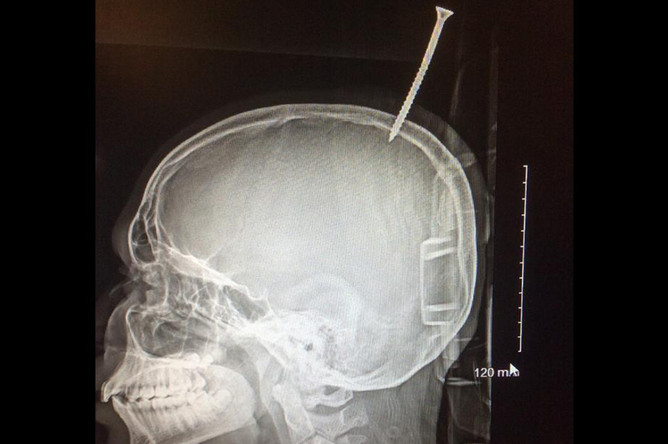

В миллиметре от смерти: ребенок выжил с шурупом в мозге

Нейрохирурги в США извлекли из черепа ребенка 15-сантиметровый шуруп